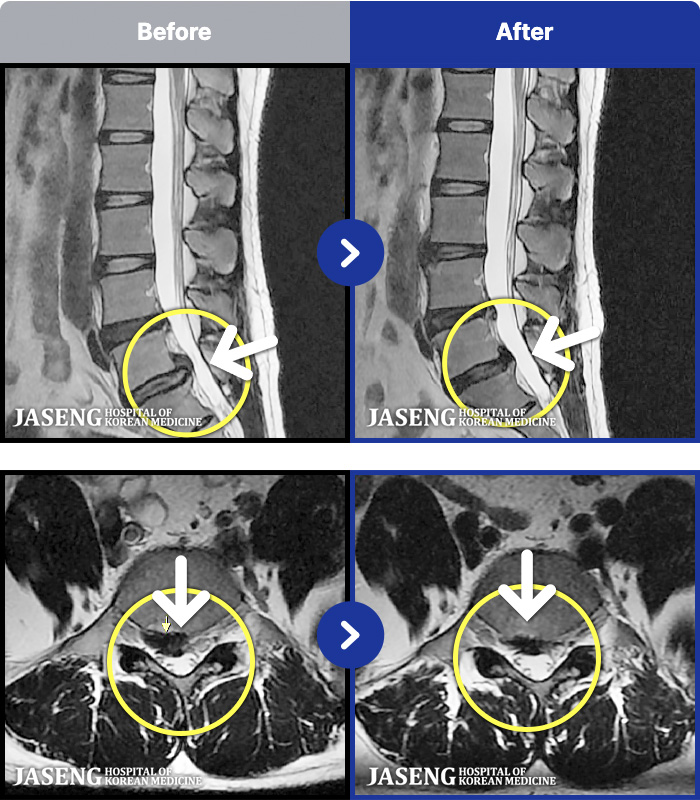

54 MRI ũ ʸ Ȯϼ.

ȯںп Ǹ ǿ ԿǾ, ο ġ ۿ Ƿ ġḦ Ͻñ ٶϴ.